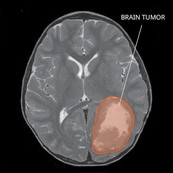

Primitive Neuro-Ectodermal Tumors (PNET)

Primitive Neuro-Ectodermal Tumors (PNET) are very rare, fast-growing tumors. PNET is a group of tumors that form in the ectoderm, the outermost layer of cells of an embryo in early development. Learn more about PNET.